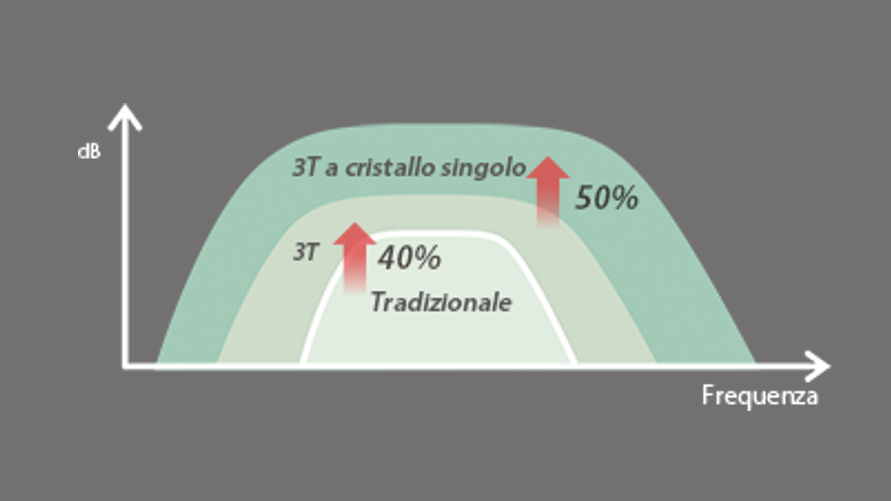

Trasduttori